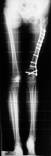

Follow Up

Left tibia lengthening with fixator in place

Lengthening tibia on Xrays in progress

Lengthening proceeding

Converted to immediate exchane nail after 65mm lengthening